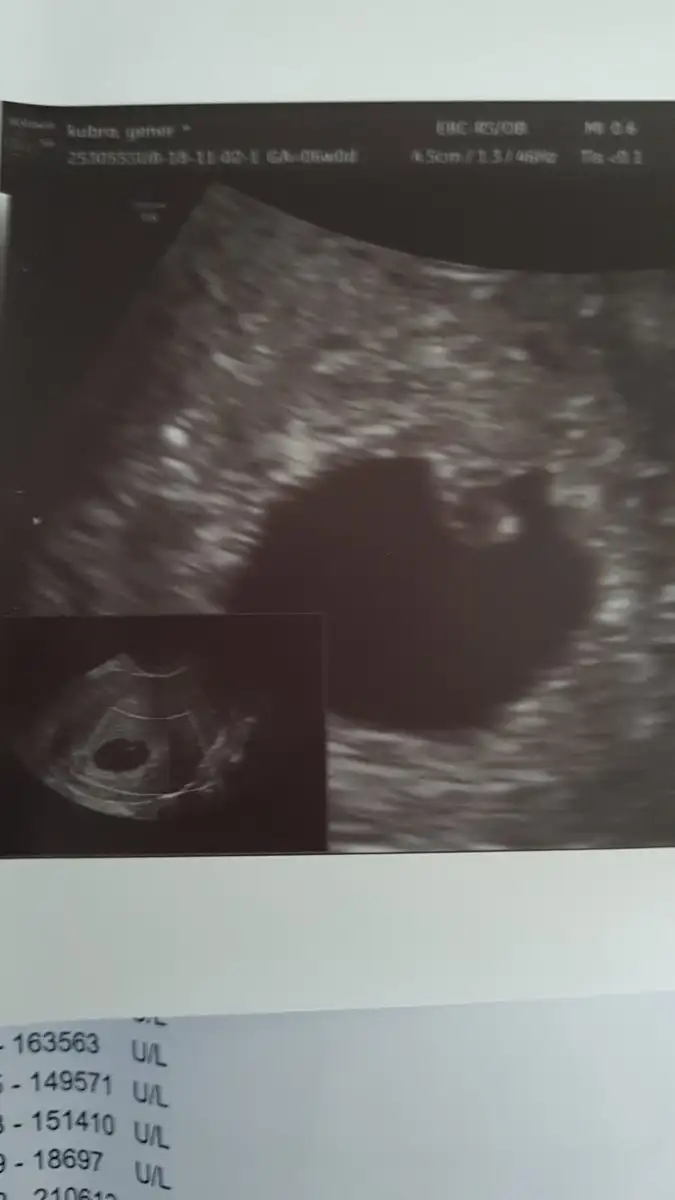

Bence olsa dr. Söylerdi canım bu tek gibi duruyor.Kızlar bu benim ultrason kagidim yolk sac ve ucunda bebek var fakat kesenin kenarında bi yuvarlak daha var acaba o ikiz olabilr mi ordaki ne kafam karisti

Hayır bende diyorum doktor söylerdi ama kenardakini çözemedimBence olsa dr. Söylerdi canım bu tek gibi duruyor.